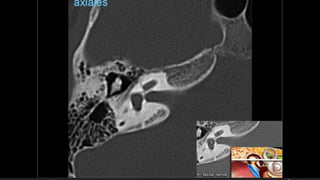

Evaluación Imagenologica

• #38 Izqu. AXIAL-- fxLongitudinal perdonan la capsula otica (laberinto oseo) Centro AXIAL fx trnasversa lascuales tperdonan el lab erinto oseo Dere: MIXTA – tmp perdona